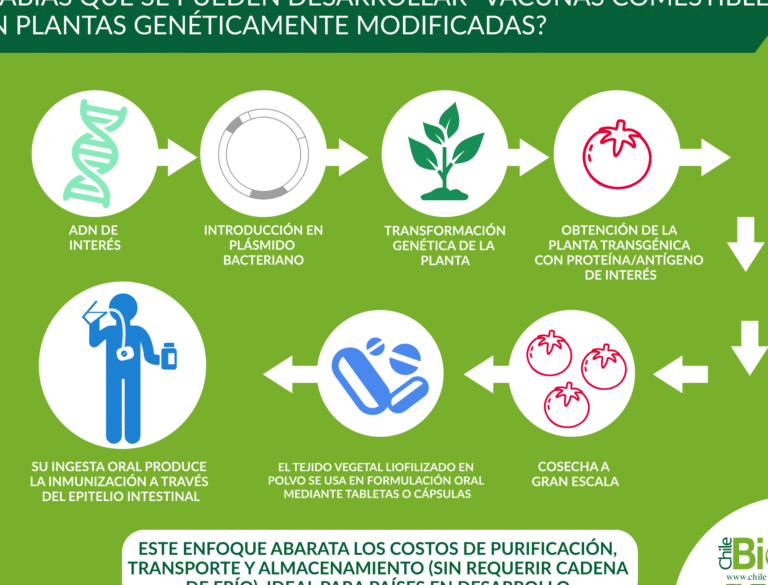

El representa una innovadora frontera en la biotecnología médica, ofreciendo una alternativa accesible y sostenible a los...